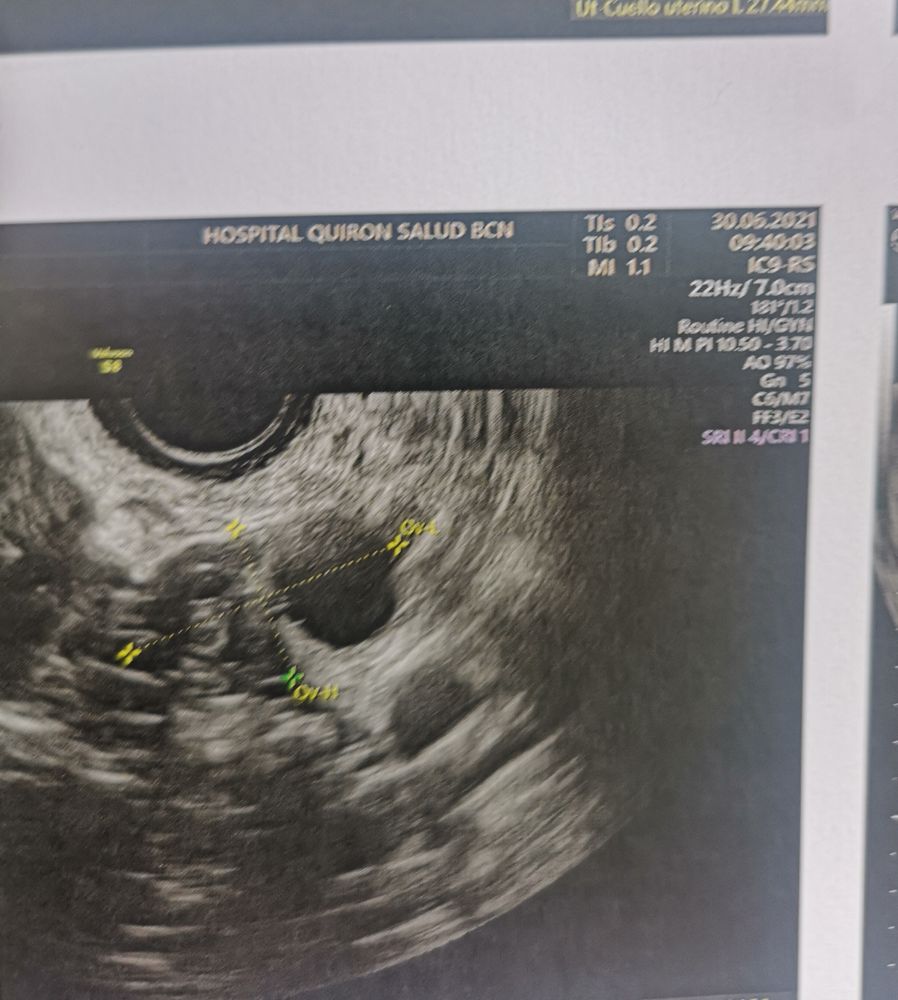

Девочки очень интересуют ваше мнение. Ситуация такая у меня ранней О не бывает, самая ранняя была за полтора года планирования на 12 дц. Обычно 14-16 дц. В пя раньше в ля позже. Сегодня 12 дц с 9 дц делаю тесты на О, тесты мне всегда отлично показывают О. Тесты никакие. Меряю бт и она растёт. По ощущениям О не было, выделения яб. Ради интереса пошла сегодня на узи и узист говорит О была и что есть жт 16*17, эндик 13 мм, но он у меня всегда отличный, сразу скажу этому узисту я не верю, так как он уже путал дф и жт. Брала запись к другому но почему то попала к этому. Ваше мнение это жт иди дф? Была О или ждать ее и делать дальше тесты? Я реально запуталась.